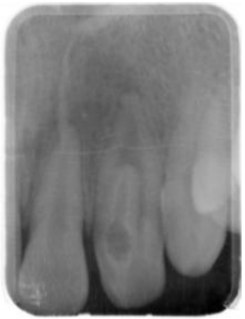

69.下圖中左側門牙的變異為何?

(A)Dens evaginatus (B)Dens invaginatus (C)Peg lateral (D)Talon cusp